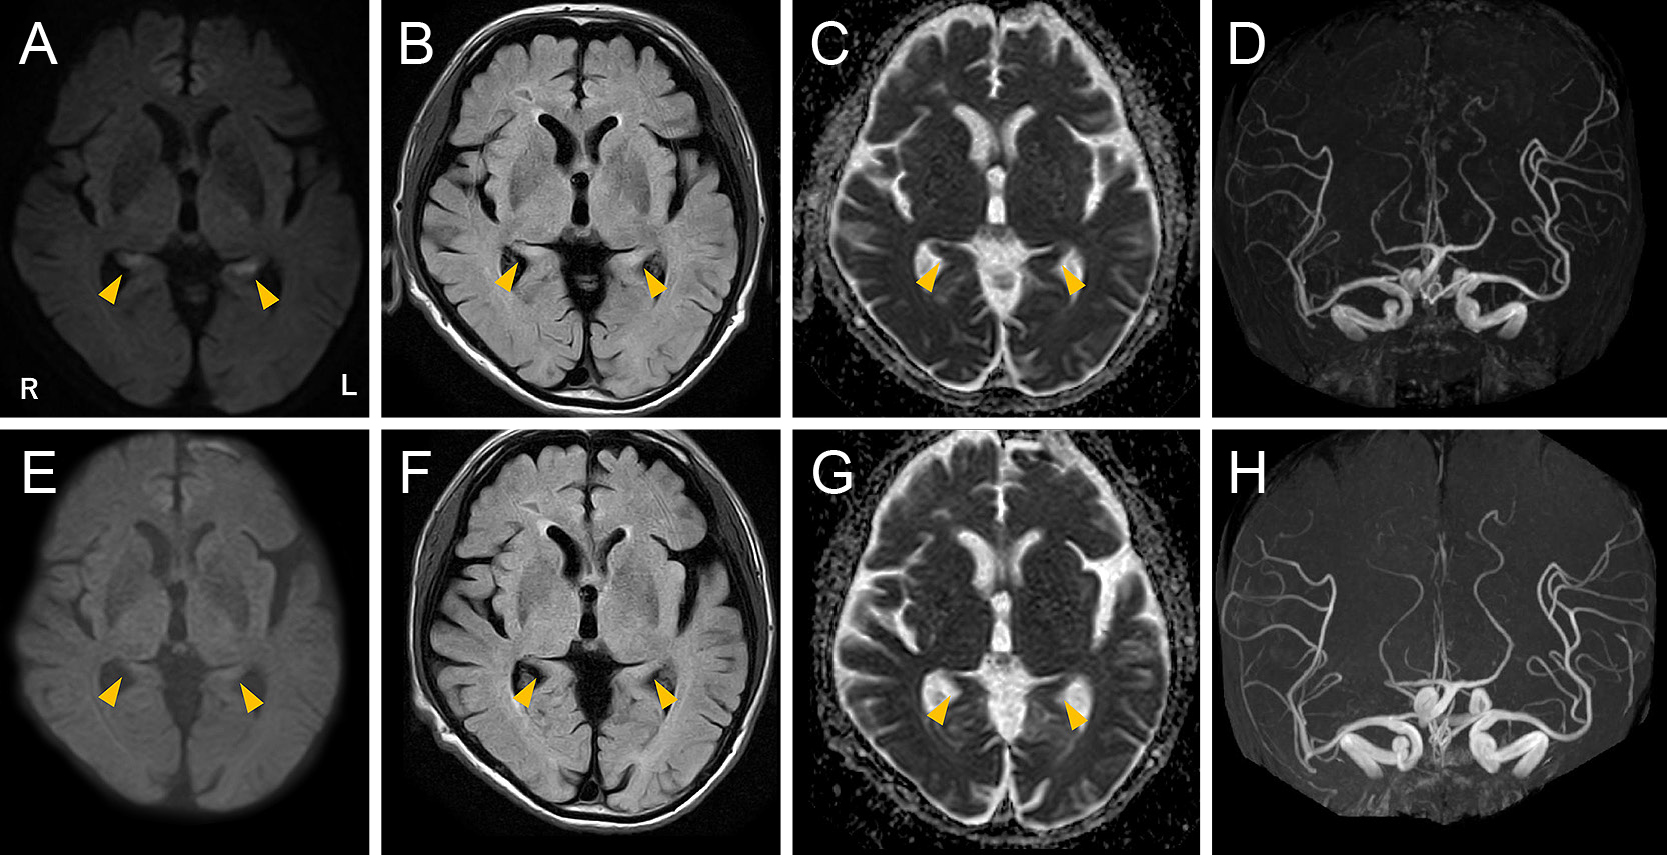

慢性炎症性脱髄性多発神経根炎でステロイドを投与中にヒトヘルペスウイルス6A脳炎を発症した89歳男性の症例

A case report: an 89-year-old man taking prednisolone for chronic inflammatory demyelinating polyradiculoneuropathy diagnosed with human herpesvirus 6 variant A encephalitis

吉武 沙和佳, 朴 文英, 佐久間 美帆, 市野瀬 慶子, 水谷 真之, 渡邊 睦房

Sawaka Yoshitake, Bunei Paku, Miho Sakuma, Keiko Ichinose, Saneyuki Mizutani, Mutsufusa Watanabe

2026/02/13